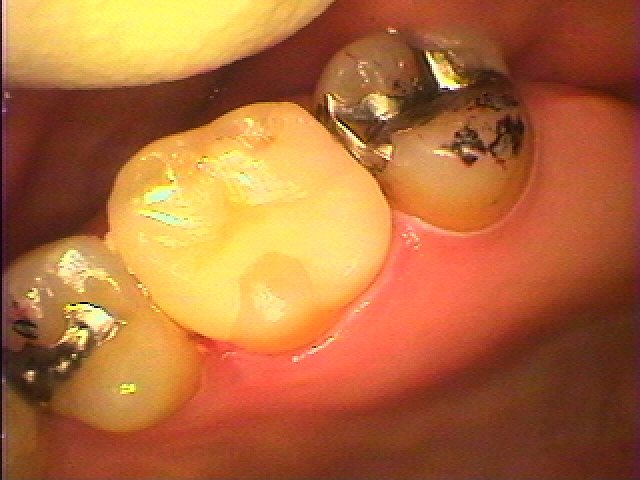

左上6番のインレーを外して虫歯治療を行っていきます セレックプライムスキャンを用いたセラミック治療|お知らせ |広島市安佐南区の歯科医院 左上6番のインレーを外して虫歯治療を行っていきます セレックプライムスキャンを用いたセラミック治療 トップ お知らせ・ブログ お知らせ 左上6番のインレーを外して虫歯治療を行っていきます セレックプライムスキャンを用いたセラミック治療 左上6番のインレーを外して虫歯治療を行っていきます セレックプライムスキャンを用いたセラミック治療 銀歯を外していきます この銀歯を白くしたいとのこと 銀歯を外していきました ひどくはないですが少し悪くなっています 虫歯を除去して型取りを行います セレックセラミックにて修復しています このようにきれいな白いセラミックが入りました 喜んでいただきました Web診療予約 初めての方へ 選ばれ続ける理由 院内設備について 歯が痛いしみる一般歯科 歯がぐらぐらする歯周病 健康な歯を保ちたい予防歯科 子供の虫歯予防をしたい小児歯科 銀歯をセラミックに審美歯科 白い歯を目指しませんか?ホワイトニング 矯正専門医がいるので安心矯正歯科 抜けた歯を補いたいインプラント・入れ歯 医院案内 スタッフ紹介 メリィハウス歯科クリニックオフィシャルホームページ ラベンダー歯科クリニックオフィシャルホームページ お知らせ・ブログ ホーム 診療科目 一般歯科 歯周病治療 予防治療 小児歯科 審美治療 ホワイトニング 矯正歯科 入れ歯・インプラント マウスピース矯正 初めての方へ 院長・スタッフ 設備紹介 医院案内・アクセス メニューを閉じる